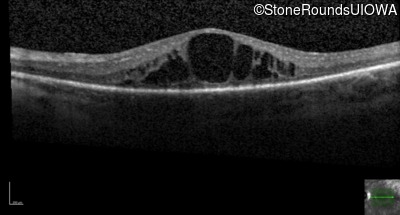

Optical Coherence Tomography - Right - 20/60 -1

Exemplar / OCT Stack